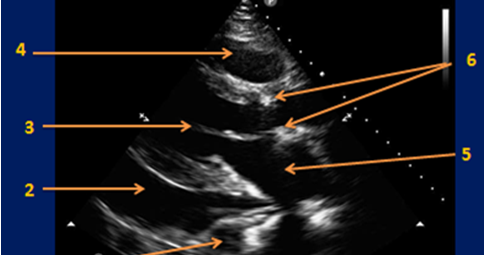

Σύγχρονο διαδικτυακό βιβλίο καρδιολογίας: Νόσοι του ...

Σύγχρονο διαδικτυακό βιβλίο καρδιολογίας: Νόσοι του ... from i.ytimg.com

Σύγχρονο διαδικτυακό βιβλίο καρδιολογίας: Νόσοι του ... from 2.bp.blogspot.com